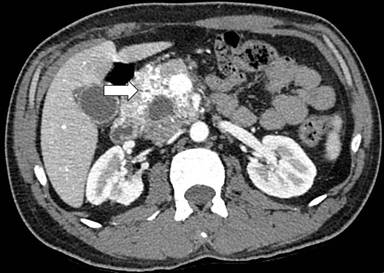

CECT of the upper abdomen revealed bulky head and uncinate process of pancreas with altered attenuation and abnormal enhancement with multiple vascular channels within and around the head and uncinate process of pancreas with abnormal enhancement in adjacent wall of the duodenum and a cystic lesion in the head of the pancreas with haziness and stranding in the peripancreatic fat (Figure 2). Endoscopic ultrasound revealed multiple dilated vascular channels in the head of the pancreas (Figure 3) with portal vein thrombosis.

Figure 3. CT angiography of the pancreatic head showing the increased vascularity in arterial phase. |